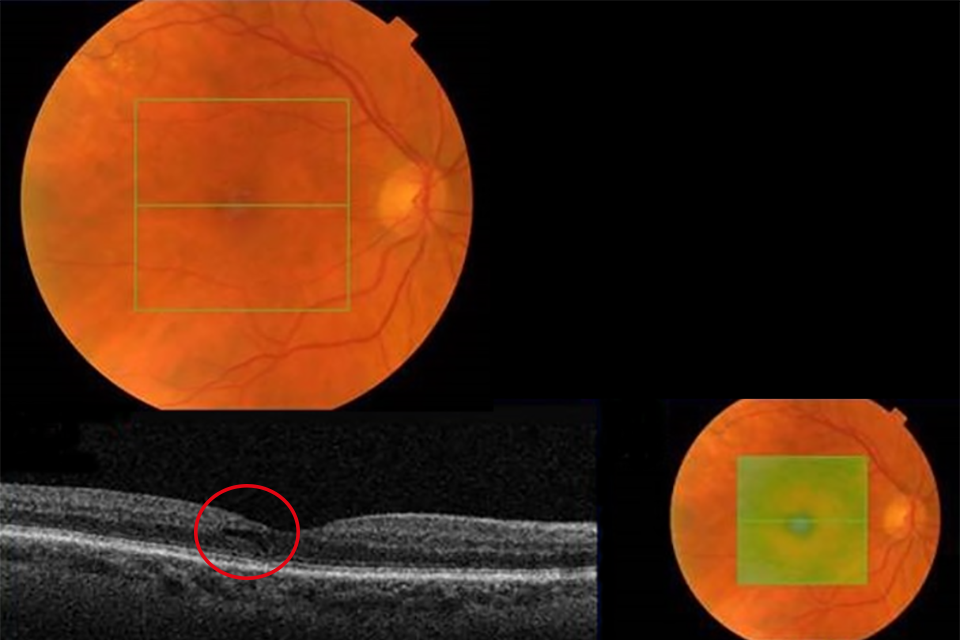

Example 2 R1M1 and OCT negative with exudate circled in red

Example 2 has:

- photographic surrogate markers for M1, for example exudate within 1 DD

- no intraretinal cysts

- no change in foveal contour

- no diffuse thickening

If the surrogate marker for M1 is due to microaneurysms or haemorrhage within 1 DD of the centre and a visual acuity (VA) of 6/12 or worse, the OCT grader can return these to routine digital screening (RDS) if they believe the reduced vision is not due to diabetic maculopathy. In these cases, the M1 would be downgraded to M0 and relevant notes made in the screening episode to support the decision.

Outcome: follow up in digital surveillance (DS).